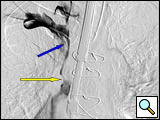

Figure 2B: Selective venogram of the right subclavian vein taken from the right brachial catheter visualizing the SVC junction with a small venous "trickle" (yellow arrow) draining into the SVC. There is extensive thrombus just at the tip of the infusion catheter and blue arrow.

The glide wire usually is advanced without difficulty through the soft clot.